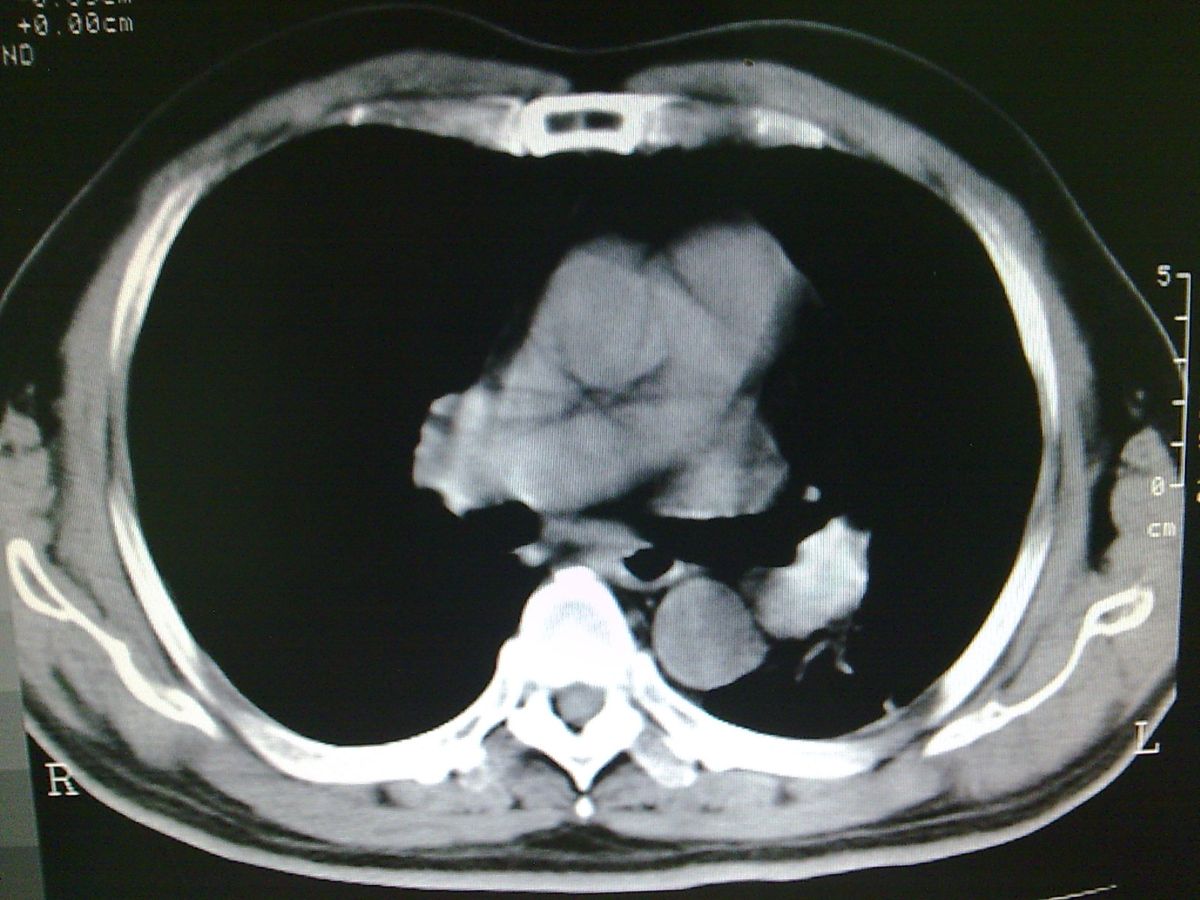

标题: CT19282:男性,70岁,咳血, [打印本页]

标题: CT19282:男性,70岁,咳血,

图片少了些,考虑周围性肺癌

考虑周围性肺癌

周围型肺癌。

考虑左下肺周围性肺癌。

考虑左下周围型肺癌可能性大。

考虑左肺下叶周围型肺癌可能。